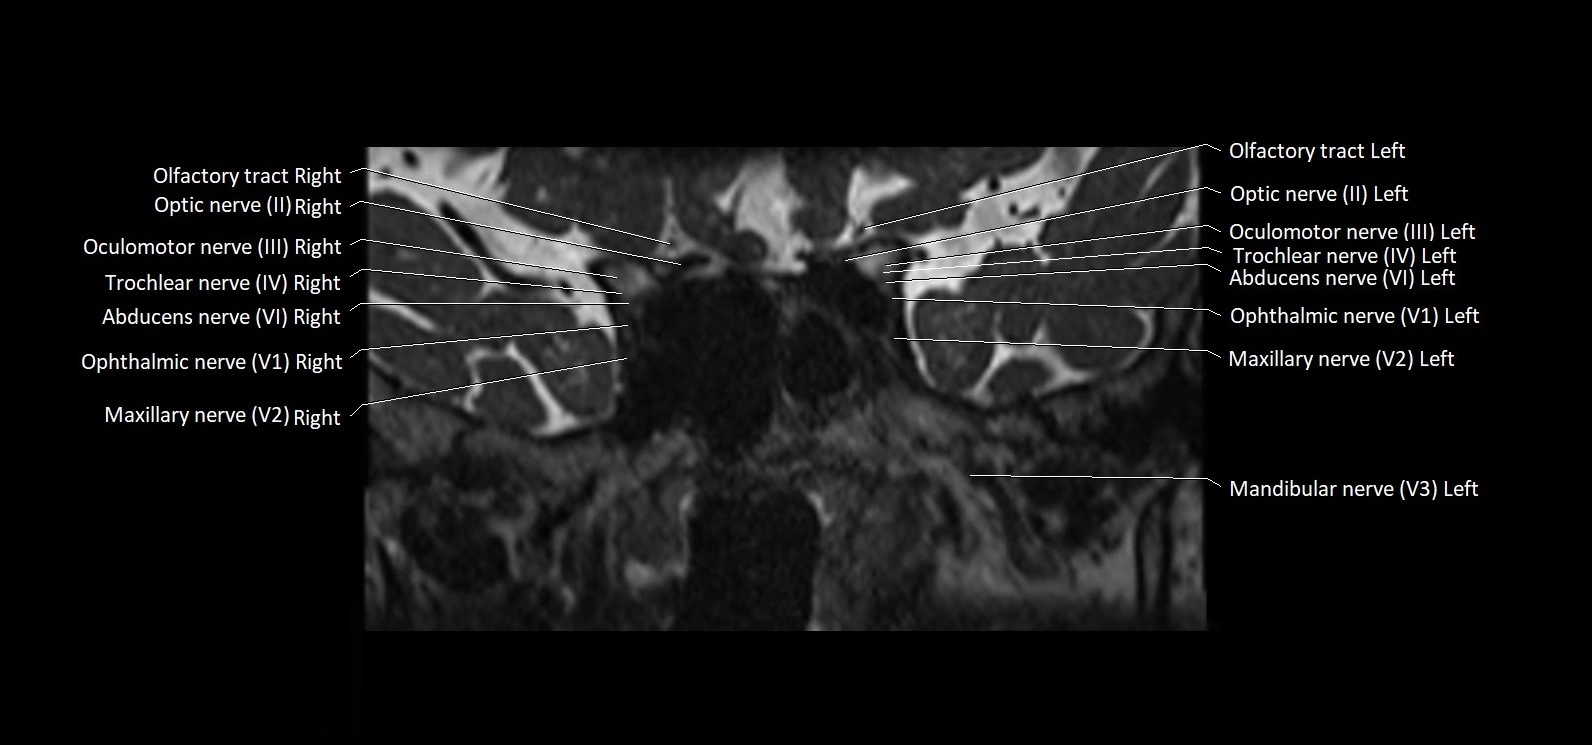

MRI Appearance

• The abducens nerve is a small, thin, linear structure

• Best visualized on high-resolution T2-weighted 3D MRI sequences (e.g., FIESTA or CISS)

• Seen as a hypointense (dark) line running from the brainstem at the pontomedullary junction, traversing the prepontine cistern, and entering Dorello’s canal under the petrosphenoidal ligament, then into the cavernous sinus, and finally the orbit

• May be challenging to visualize in standard MRI due to its small size

• Pathology may be inferred by absence, displacement, or enhancement of the nerve

MRI images

image